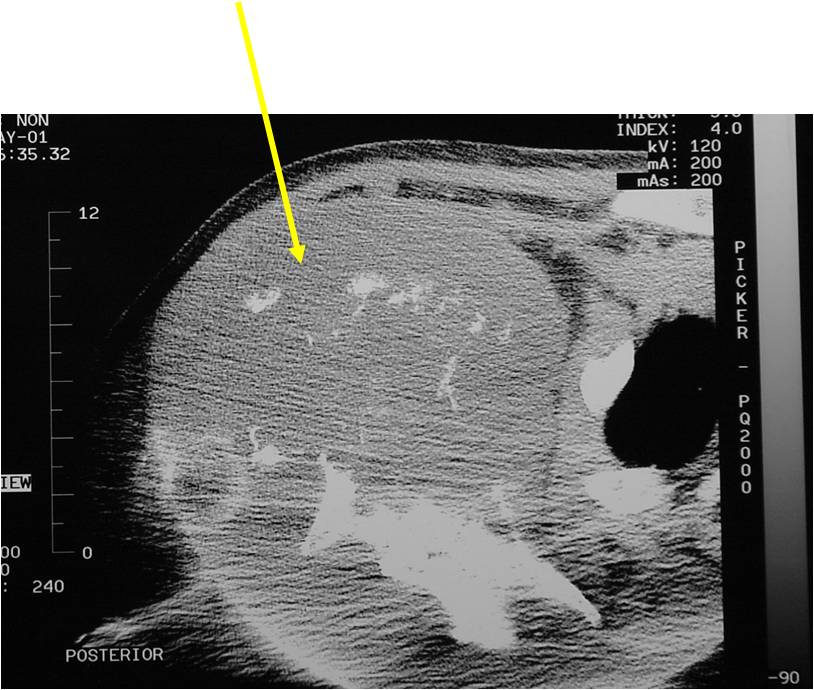

Radiology emulates pathology: Biphasic Tumor

- One region low grade chondrosarcoma

- Second more aggressive area with bone destruction, lysis of calcification, soft tissue mass

- Cortical permeation and a soft tissue mass in 70% of cases

Characteristically abrupt transition between chondroid tumor and dedifferentiated, lytic component

(Right Arrow)Aggressive Lytic Area (Dedifferentiated Sarcomatous Component) Cortical Destruction Soft Tissue Mass without Calcification